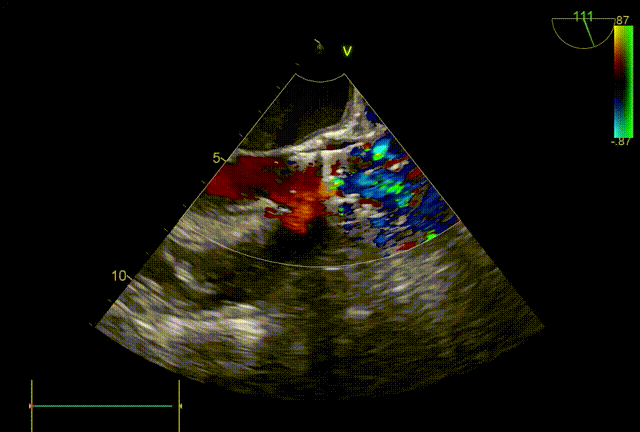

术后即刻TEE

主动脉瓣短轴切面

主动脉瓣长轴切面

术后即刻TEE示:主动脉瓣膜峰值血流速为1.2m/s,最大压差为5mmHg,平均压差为2mmHg。未见明显人工主动脉瓣反流及瓣周漏。